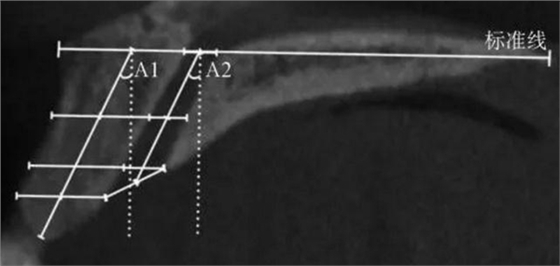

(1)正中矢狀面(圖1~3)。所使用的測(cè)量參數(shù)及其定義如下所述。鼻腭管高位直徑(S1):標(biāo)準(zhǔn)線交鼻腭管處的管徑;鼻腭管中位直徑(S2):鼻腭管長(zhǎng)軸中點(diǎn)處的管徑;鼻腭管低位直徑(S3):管后壁腭側(cè)骨最低點(diǎn)至對(duì)應(yīng)管前壁的水平管徑;切牙孔開(kāi)口直徑(S4):管后壁腭側(cè)骨最低點(diǎn)至唇側(cè)骨低位厚度和管前壁交點(diǎn)的直線距離。唇側(cè)骨高位厚度(T1):S2平面處唇側(cè)骨板水平厚度;唇側(cè)骨中位厚度(T2):S3平面處唇側(cè)骨板水平厚度;唇側(cè)骨低位厚度(T3):唇側(cè)骨最凸處骨板水平厚度。鼻腭管長(zhǎng)度(L1):S1與S4中點(diǎn)間的距離;唇側(cè)骨長(zhǎng)度(L2):唇側(cè)骨下端最低點(diǎn)經(jīng)T1、T3中點(diǎn)至標(biāo)準(zhǔn)線的直線長(zhǎng)度。鼻腭管傾斜角度(A1):L1和標(biāo)準(zhǔn)線的垂線所成角度;唇側(cè)骨傾斜角度(A2):L2和標(biāo)準(zhǔn)線的垂線所成角度。

A1:鼻腭管傾斜角度;

A2:唇側(cè)骨傾斜角度。

圖 3 矢狀面鼻腭管傾斜角度測(cè)量方法

Fig 3 Measurements ofinclination angle of the nasopalatine canal